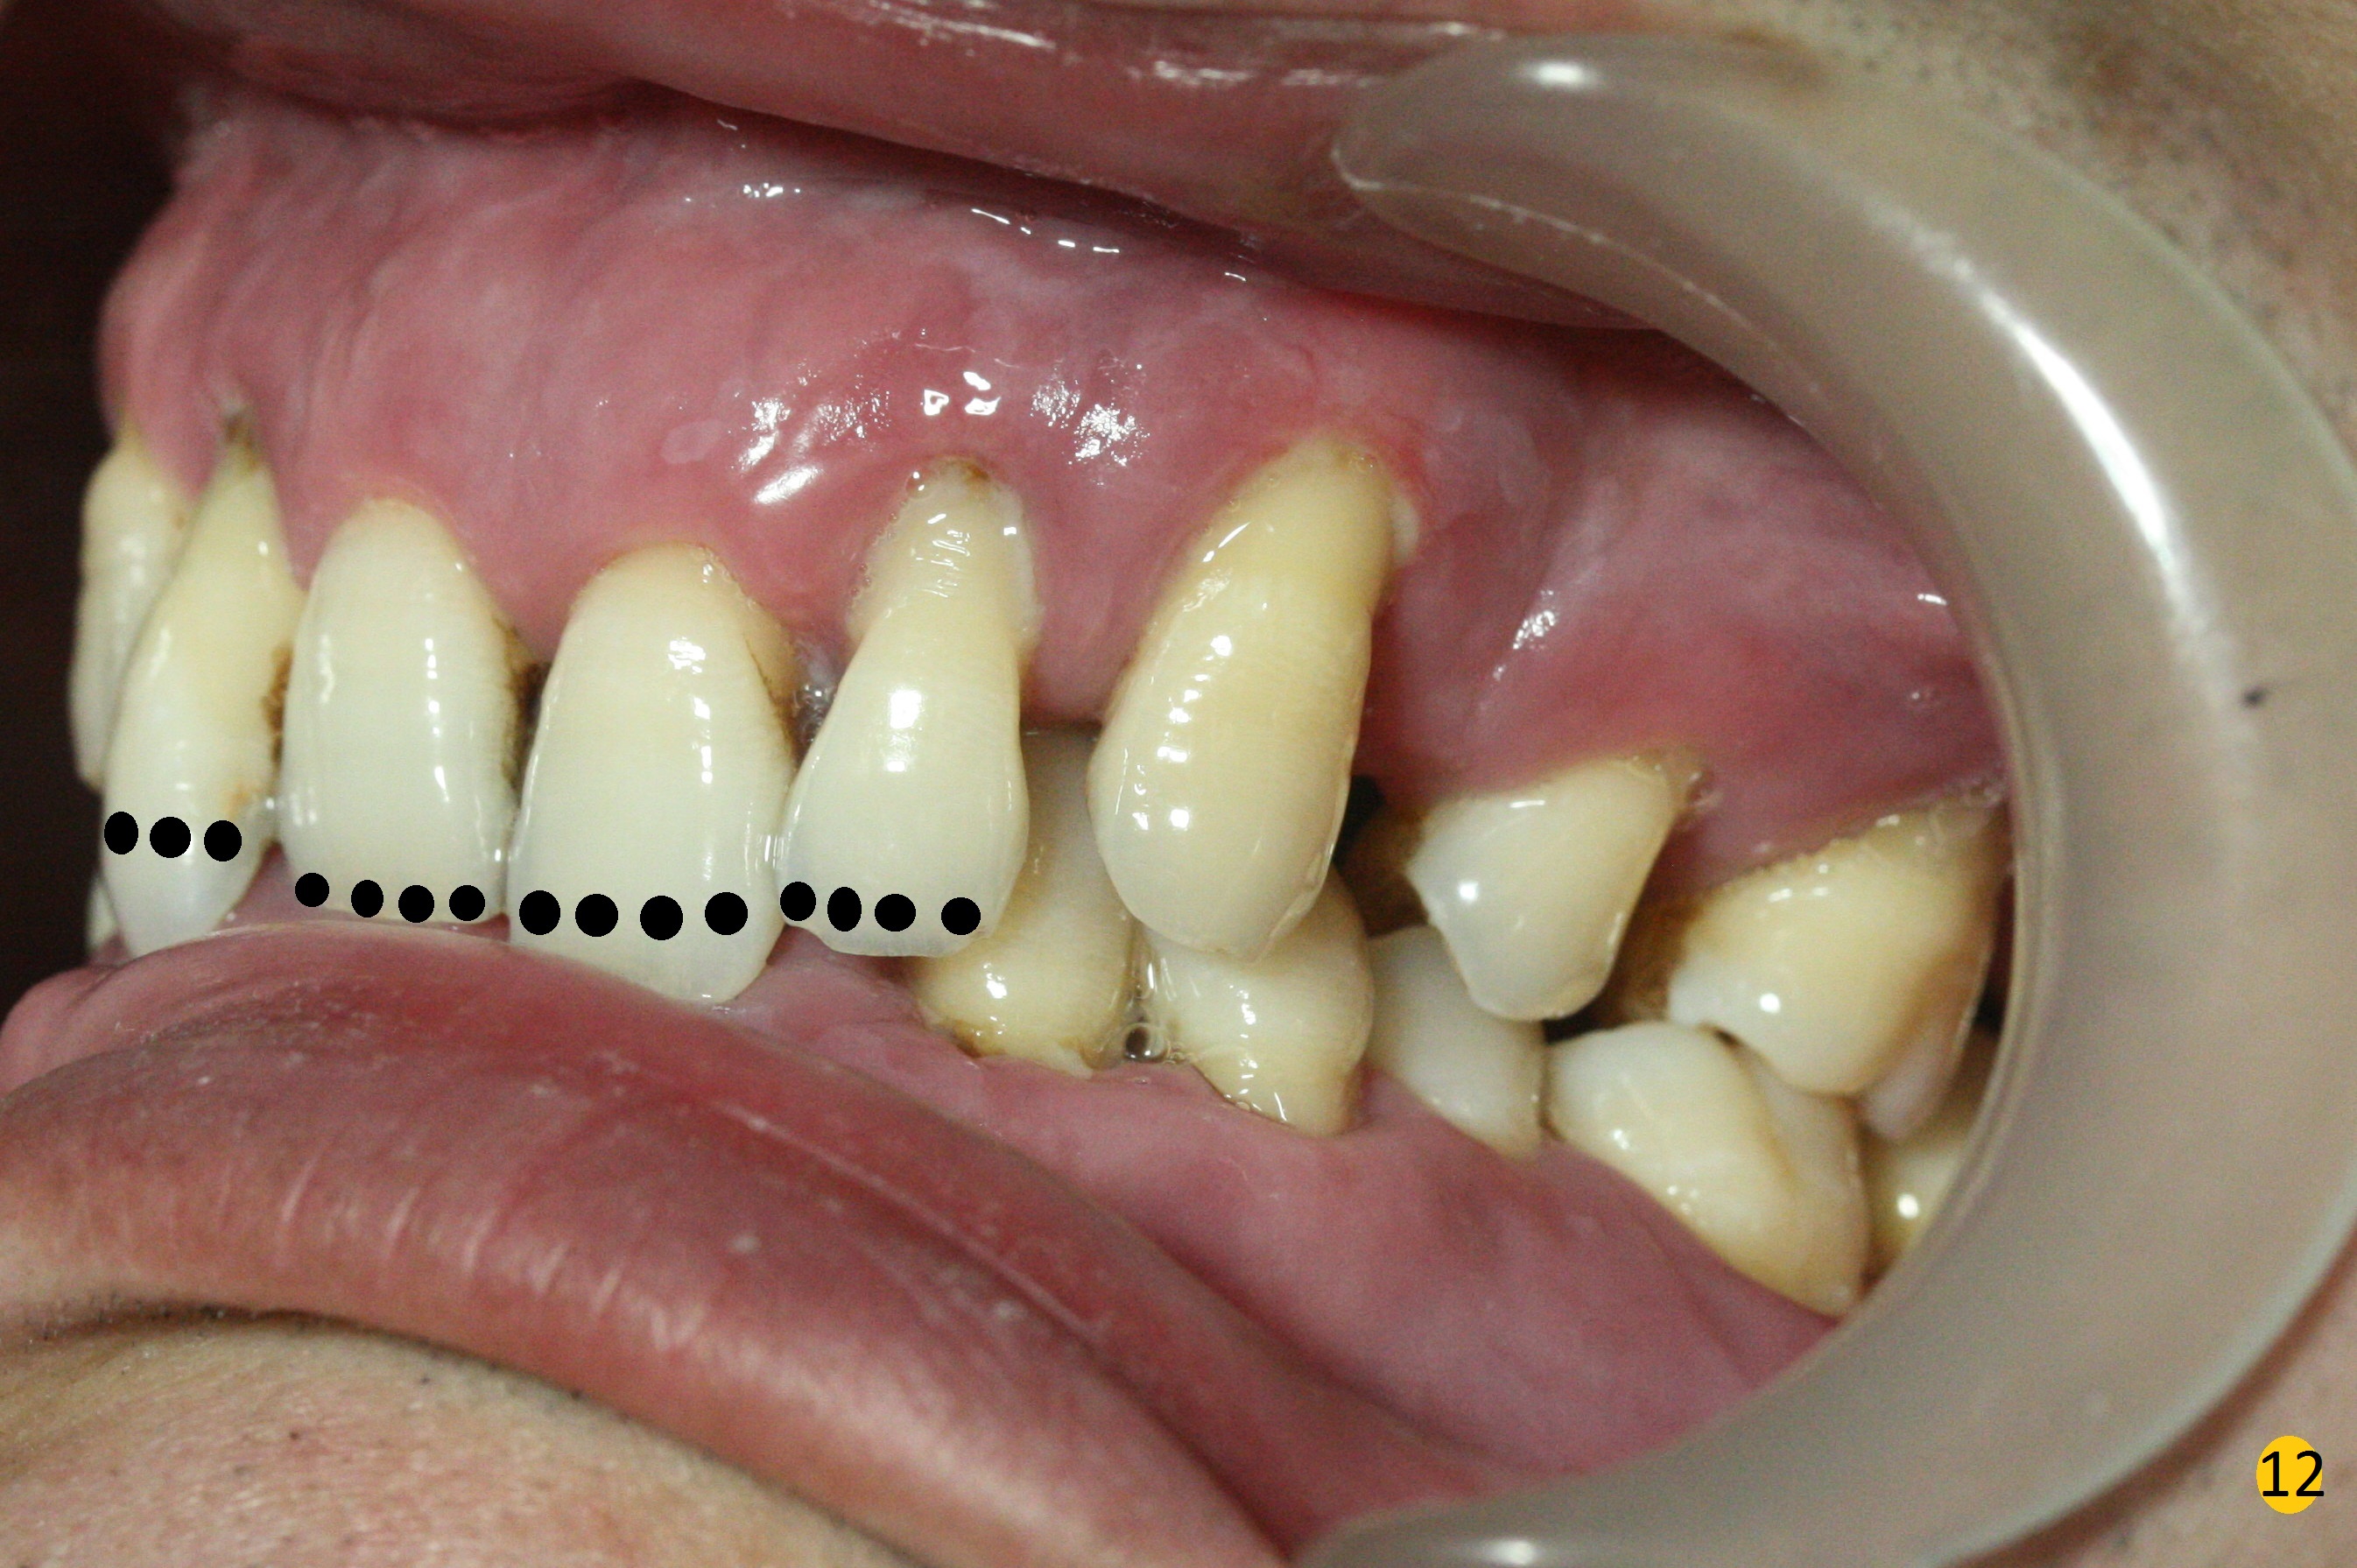

Class II Division II malocclusion (Fig.2,6) will make it difficult to restore #23-26 implant-supported FPD. Although the teeth #7-10 may need to be replaced later (Fig.7,8), enameloplasty will be conducted for #7-10 (Fig.9 white area; Fig.12 black circles (gross reduction)) prior to #23-26 extraction and implant placement (Fig.10). To be flexible in restoration (angulation) and possible future hybrid denture, 2-piece narrow implants will be placed (3.0 or 3.3 mm) instead of 1-piece ones. In fact CBCT shows that the narrowest regular implant (3.8 mm) can be placed in the lower anterior region (Fig.13-15).